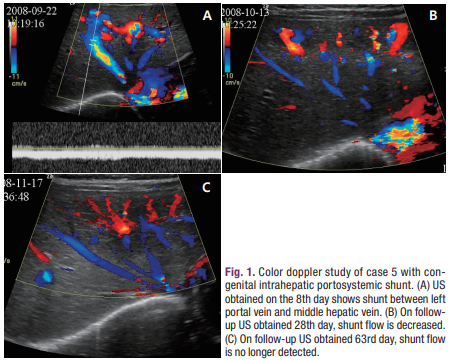

환아 5는 39주 1일에 2,500 g으로 출생하여 자궁 내 성장지연을 보였으며, 산전 초음파 검사에서 우측 간엽에서 비정상적인 관상 구조가 관찰되어, 생후 8일째 시행한 복부 초음파에서 간 좌엽의 좌측 간정맥과 좌측 문맥 사이 및 중간 간정맥과 좌측 문맥 사이의 단락이 진단되었고 생후 2개월에 소실을 확인하였다(Fig. 1). SGOT/SGPT, 빌리루빈의 상승은 없었다.

신생아의 4명은 초음파와 CT를 시행하였으며 성인 환자는 CT만 시행하였다. 5명 모두 좌간엽에 단락을 보였다. 신생아의 4명은 좌간엽의 원위부에 간내 문맥정맥단락이 있었고 이중 3명은 중정맥과 좌문맥(Fig. 1), 1명은 좌정맥과 좌문맥사이에 단락이 있었다. 이들 중 1명은 좌간엽에 다발성의 단락이 보였다(Fig. 2). 증례 5의 성인 환자는 좌문맥과 좌정맥이 직접 연결되는 정맥관이 남아있는 형태의 간내 문맥정맥단락을 보였다(Fig. 3).

단락이 있는 간정맥은 5명 중 3명은 중정맥, 2명은 좌정맥이었다. 간문맥은 모두 좌문맥의 제대부분(umbilical portion)과 연결이 있었다. 신생아의 2명에서만 추적검사를 시행하였는데 증례 1의 환아는 3개월 후 초음파에서 단락이 소실되었고 증례 2의 환아는 6개월 후에 시행한 CT에서 간내 문맥정맥 단락이 자연 소실되었다(Fig. 1E) (Table 2). 이 두 환아는 초기에 황달과 패혈증으로 입원하여 치료받고 치유가 되어 퇴원을 했으며 추적검사를 시행할 당시에는 특별한 문제는 없었다.